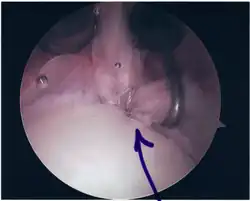

Following inspection and determination of the extent of injury, the basic labrum repair is as follows.

- The glenoid and labrum are roughened to increase contact surface area and promote re-growth.

- Locations for the bone anchors are selected based on number and severity of tear. A severe tear involving both SLAP and Bankart lesions may require seven anchors. Simple tears may only require one.

- The glenoid is drilled for the anchor implantation.

- Anchors are inserted in the glenoid.

- The suture component of the implant is tied through the labrum and knotted such that the labrum is in tight contact with the glenoid surface.